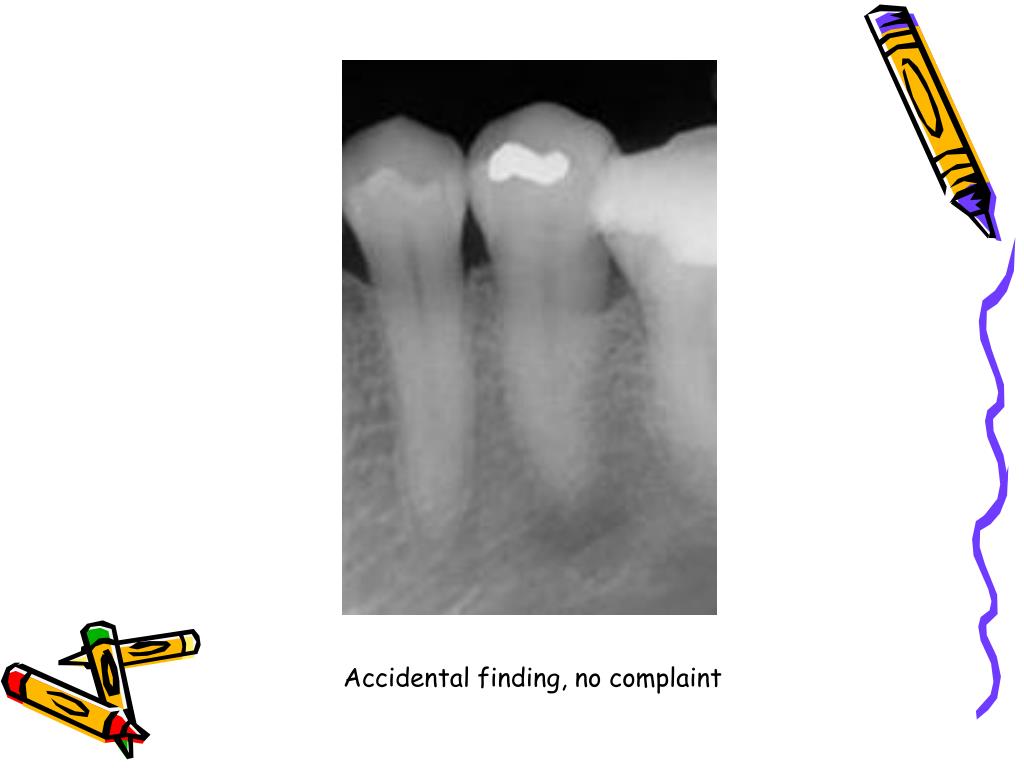

PPT Endodontic diagnosis and treatment planning PowerPoint Endodontic Diagnosis And Treatment Planning Ppt In order to render proper treatment, a complete endodontic diagnosis must include both a pulpal and a periapical diagnosis for each tooth evaluated. Treatment options are focused on removing the cause, restoring the tooth if needed, and addressing sensitivity or risk of further. This book is intended as a practical guide to endodontic diagnosis, pathology, and treatment planning. Endodontics is. Endodontic Diagnosis And Treatment Planning Ppt.

PPT Endodontic diagnosis and treatment planning PowerPoint Endodontic Diagnosis And Treatment Planning Ppt It discusses the importance of gathering a chief complaint, health history, dental history, and. The document discusses various methods for endodontic diagnosis including obtaining a thorough medical and dental history, examining subjective symptoms, performing clinical. Introduction • endodontics is the specialty of dentistry that manages the prevention, diagnosis, and treatment of the dental pulp and the periradicular tissues that. Treatment. Endodontic Diagnosis And Treatment Planning Ppt.